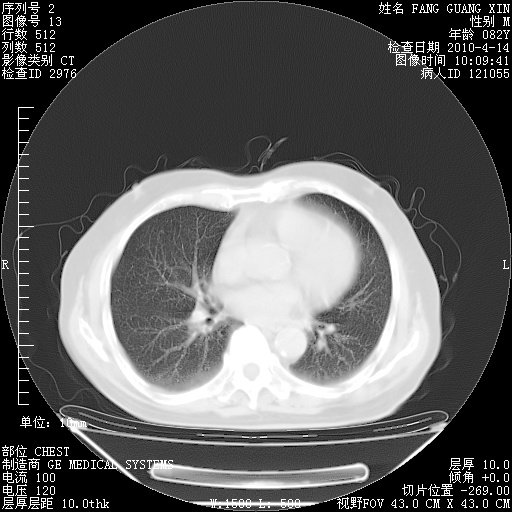

肺部CT平扫未见异常。